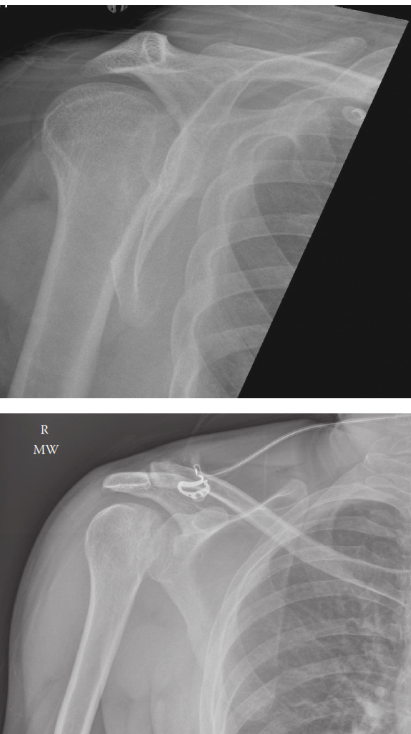

Management of Proximal Humerus Fracture 1. Describe these radiographs. Show Answer Show Explanation 2. How wo…

You are called to the emergency department to see a 60-year-old man who has fallen while running, injuring hi…

A 45-year-old man with epilepsy is brought to the emergency department following a sei- zure. He complains of…